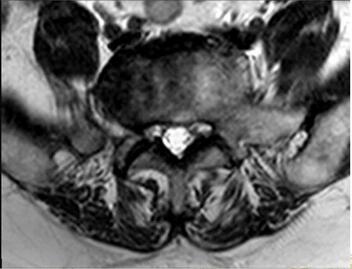

4.輔助檢查:MRI顯示腰椎退行性變:L4-5椎間盤脫出(左側(cè)隱窩型),伴左側(cè)側(cè)隱窩狹窄,相應(yīng)神經(jīng)根受壓,馬尾神經(jīng)受壓;局部腰椎管狹窄。

診斷結(jié)果:根據(jù)患者病史、癥狀、體征及輔助檢查,目前診斷明確?,F(xiàn)患者腰腿痛明顯,伴有脊髓神經(jīng)根受壓、椎管狹窄癥狀,保守治療不能緩解,如不進(jìn)行手術(shù),壓迫癥狀會進(jìn)一步加重,甚至造成截癱。

手術(shù)方案:全麻下行“腰椎間盤摘除+腰椎管減壓植骨融合內(nèi)固定術(shù)”。取腰背部后正中縱行入路;骨膜下剝離椎旁肌,椎管減壓、植入椎弓根螺釘,保護(hù)脊髓及神經(jīng)根,摘除髓核,搔刮終板、椎間植骨并安置融合器;抱緊、安裝椎弓根螺釘、棒系統(tǒng);嚴(yán)密止血、放置引流、關(guān)閉切口。